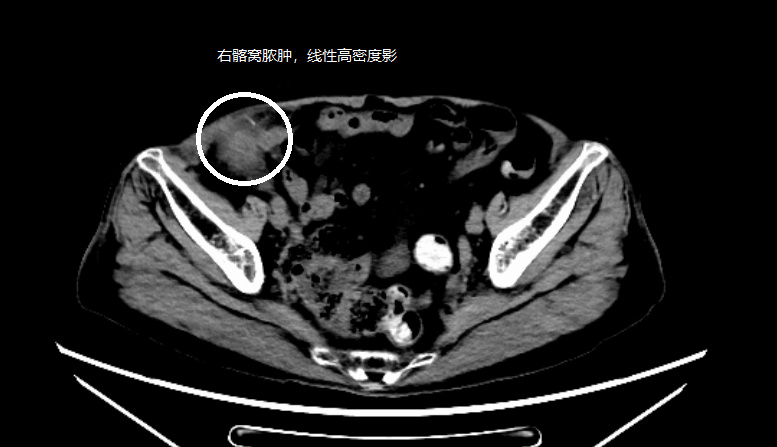

10月20日,陈奶奶(化姓)无明显诱因的右下腹疼痛,后出现发热症状,家人随即将她送至广东祈福医院消化内科就诊。初步CT检查就像一道谜题:右侧髂窝有个来路不明的包块,看起来像个“脓肿”,里面还藏着个线状的神秘高密度影。是脓肿?是肿瘤?还是……异物?

图源影像图检查

管床医生张培婵先为患者安排了增强CT,图像清晰地再次显示了脓肿及其内部的线状异物。初步排除肿瘤来源,消化内镜室团队实施了肠镜检查,操作细致,结果明确排除了结肠病变。